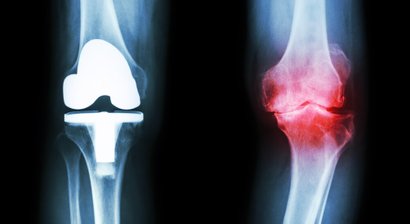

Gonarthrose (Kniearthrose)

Bei Ihrem Besuch werden Sie von mir ausführlich über sämtliche moderne Therapie-und Operationsverfahren bei Sportverletzungen (z.B. Kreuzbandriss, Meniskusriss, Bandverletzungen, Patellaluxation), Abnutzungen (Knorpelschaden, Arthrose) und Fehlstellungen beraten.

Mein fachärztlicher Schwerpunkt liegt in der Behandlung des Kniegelenks. Durch die internationale Ausbildung an einer Knieklinik, aktive Mitgliedschaft in zahlreichen wissenschaftlichen Fachgesellschaften sowie langjährige Erfahrung führe ich auch komplexe Knieoperationen (u.a. Meniskustransplantation) und Kombinationseingriffe in höchster Fallzahl in Wien durch.